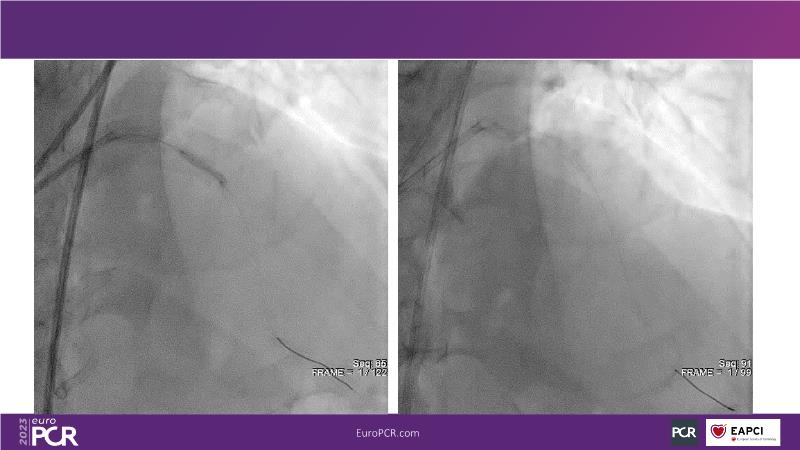

In this session, review the evolution in the use of IVL over the last few years, with a widening of the indications, observe that OCT can underestimate the number and depth of calcium fractured induced by IVL, or see that the technique is safe and effective in high-risk patients, including ACS patients, as demonstrated in real-world registries, among others!

- To understand how intravascular lithotripsy (IVL) in clinical practice has evolved over the last five years

- To evaluate the effects of IVL in different patterns of calcific coronary disease